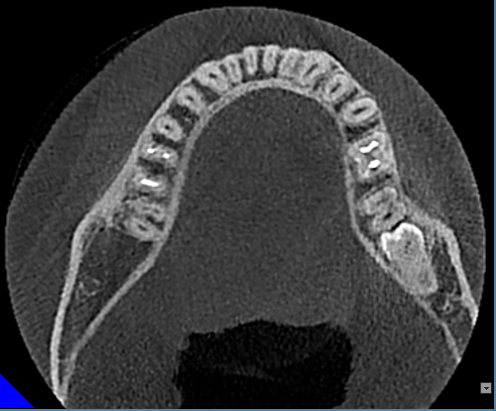

1.提供各种颌面信息及三维图像信息,精确地获得所需术前诊断信息。

2.为种植提供测量颌骨宽度、长度、密度及各种距离、角度等综合信息,以选择各种种植体尺寸及位置。

3.重要结构的定位,种植体间距离安全碰撞检测(神经管、上颌窦、病变位置等)避免手术中发生突发情况。

4.真实模拟种植体的位置,可选择任意种植型号、大小尺寸等,方便医患直观交流讨论。

5.定制手术外科导板,精确定位种植体位置及方向,提供微创及即刻种植方案